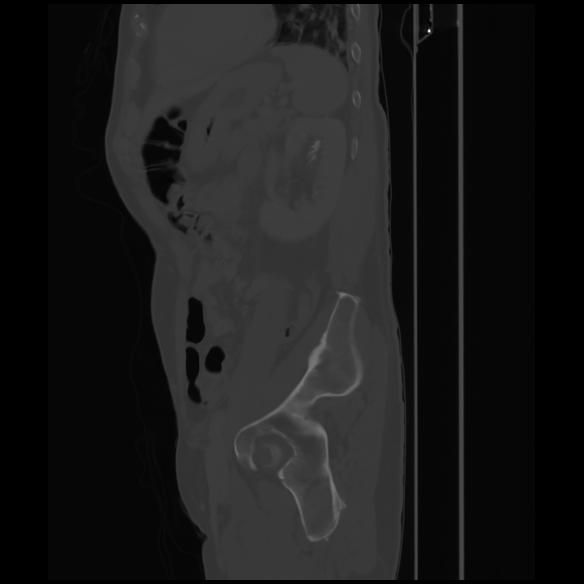

7 CUERPO,CE,Sagittal,3.000,CUERPO,Sagittal,